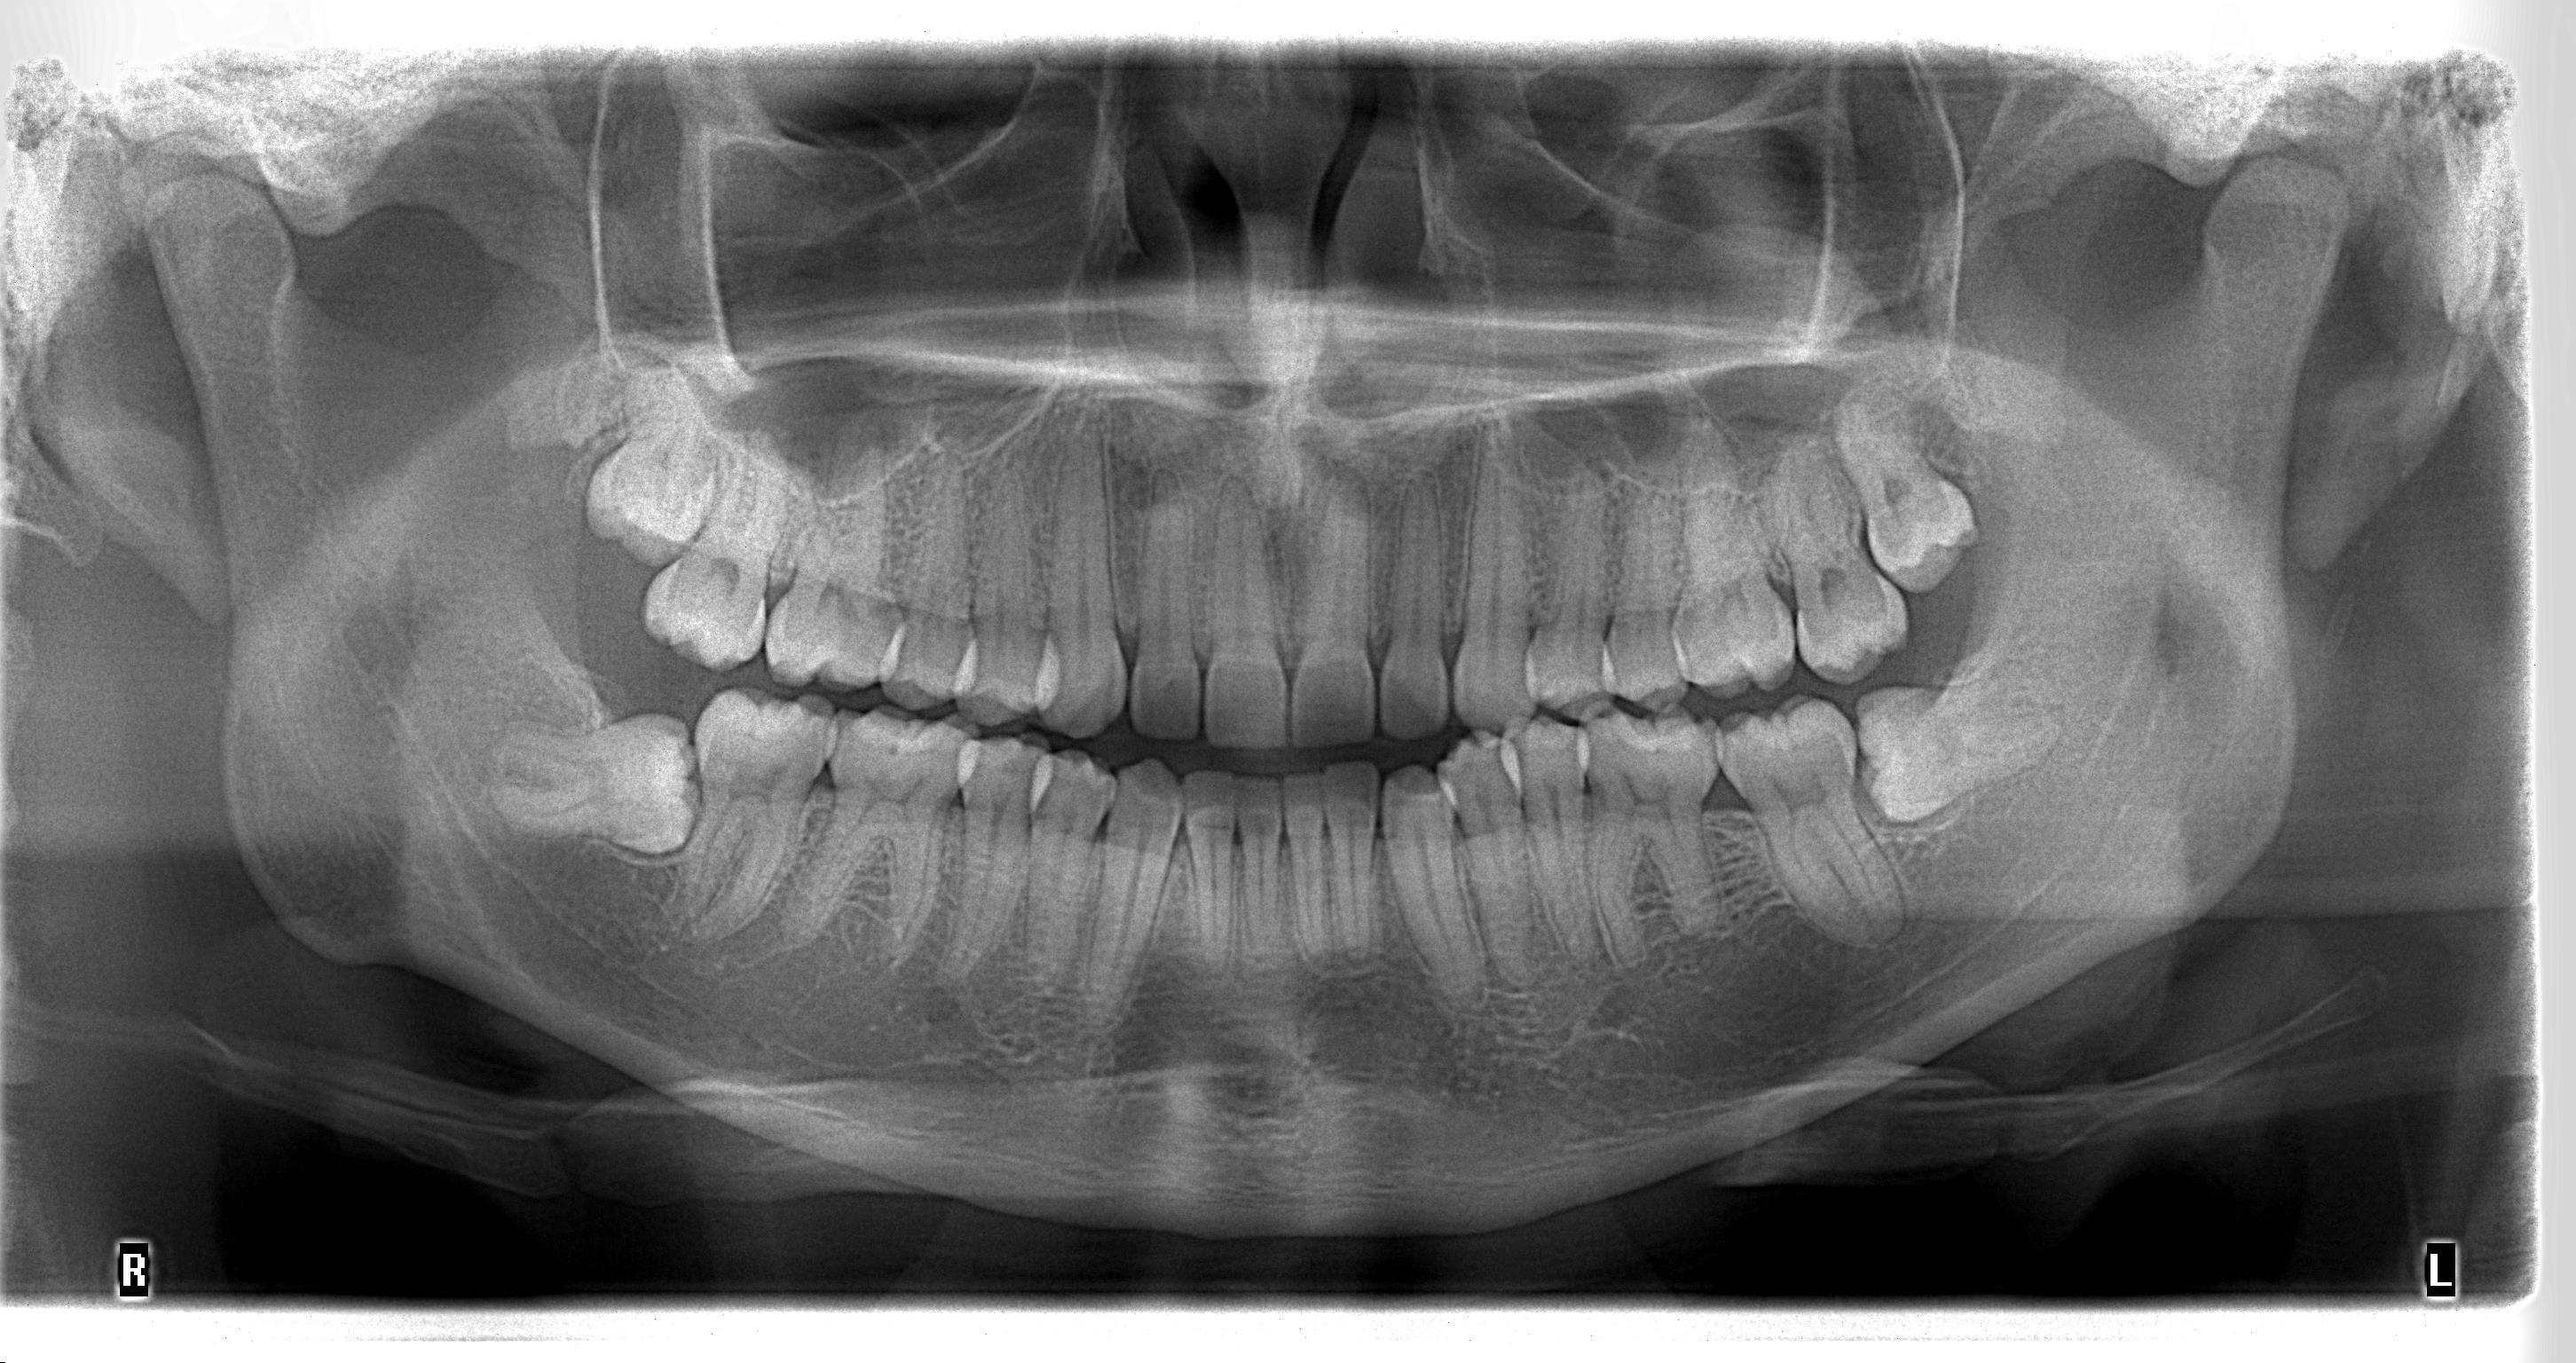

RX Panorámica

Es una radiografía que abarca la mandíbula desde un condilo hasta el condilo del lado opuesto. Deja observar todas las estructuras dentarias y sus tejidos adyacentes en una sola toma.